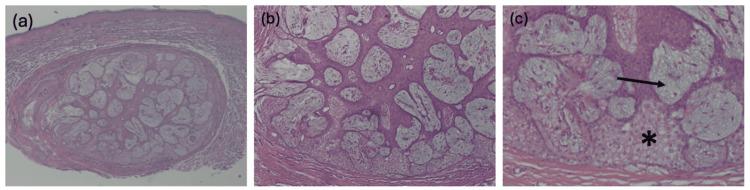

We report a case of a clinically indistinct pink papule on the midline upper back of a 77-year-old woman. Histopathological examination of the lesion revealed a unique variant of folliculosebaceous cystic hamartoma (FSCH) characterized by mucin deposits in sebaceous lobules. FSCH is a rare lesion involving a cystically dilated follicle surrounded by sebaceous glands embedded within a stromal matrix composed of mesenchymal features. Follicular mucinosis is an uncommon inflammatory disorder typically presenting as benign, idiopathic lesions in children or mycosis fungoides-associated lesions in adults. A literature review revealed no previously reported cases of FSCH involving mucinosis of our knowledge to date, making this a novel and clinically relevant histopathologic variant. This case expands the histological presentation of a rare lesion and highlights the importance of careful examination in differentiating between similarly presenting dermatological conditions. Additionally, this novel finding suggests the possibility of an unknown pathologic mechanism of mucin deposition in FSCH, warranting further research.

我们报告了一例77岁女性上背部中线处出现的临床特征不明显的粉红色丘疹病例。对该病变进行组织病理学检查发现了一种毛囊皮脂腺囊性错构瘤(FSCH)的独特变体,其特征为皮脂腺小叶中有粘蛋白沉积。FSCH是一种罕见病变,涉及一个囊性扩张的毛囊,周围有嵌入由间充质特征组成的基质中的皮脂腺。毛囊粘蛋白病是一种不常见的炎症性疾病,通常表现为儿童的良性特发性病变或成人的蕈样肉芽肿相关病变。文献回顾显示,据我们所知,此前尚无FSCH合并粘蛋白病的病例报道,这使其成为一种新的且具有临床相关性的组织病理学变体。该病例扩展了一种罕见病变的组织学表现,并强调了仔细检查在鉴别相似表现的皮肤病中的重要性。此外,这一新发现提示了FSCH中粘蛋白沉积存在未知病理机制的可能性,值得进一步研究。